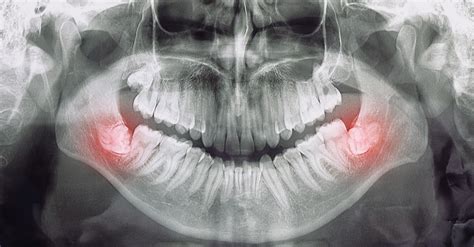

Una muela del juicio infectada puede ser una experiencia dolorosa, incluso peligrosa. Las muelas del juicio, también conocidas como cordales o terceros molares, deben su nombre a que son los últimos dientes en aparecer. Suelen empezar a erupcionar a los 17 años y no terminan de salir hasta los 23 o 25 años de edad.

Las muelas del juicio son piezas dentales que, debido precisamente a su ubicación, pueden ocasionar diversos problemas. El más común es la falta de higiene. Y es que, al encontrarse en la parte posterior de la boca, resulta algo más complejo acceder a ellas con el cepillo de dientes. Al comer, hay alimentos que se retienen en esa bolsa, ya que la higiene no se realiza correctamente al ser una zona de difícil acceso.

Pero, además, otro problema muy frecuente tiene que ver con el dolor de las muelas del juicio. Estas piezas dentales suelen salir en la edad adulta, cuando el resto de dientes ya han erupcionado. Dicho todo esto, vamos a empezar a recordar cómo son estas piezas dentales y cuál es su función en la boca. Las muelas del juicio, o cordales, son los terceros molares y las últimas piezas dentales en erupcionar, generalmente entre los 17 y 25 años.

Causas de Infección en Muelas del Juicio

Las causas más frecuentes de una muela del juicio infectada suele estar asociado con casos de infección en las encías o en los dientes.

- Caries Dental: Las caries son una causa común de infecciones dentales. Cuando las bacterias dañinas atacan el esmalte dental y penetran en la pulpa dental (la parte más interna del diente que contiene nervios y vasos sanguíneos), se puede desarrollar una infección.

- Absceso Dental: Un absceso dental es una acumulación de pus en el interior del diente o en los tejidos circundantes.

Las muelas infectadas, generalmente causadas por una infección bacteriana en el interior del diente o en sus tejidos circundantes, pueden ser dolorosas y potencialmente peligrosas si no se tratan adecuadamente.